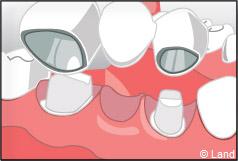

Le bridge est ensuite essayé en bouche, à l’occasion d’une nouvelle visite chez votre chirurgien-dentiste, afin qu’il s’adapte parfaitement au relief de vos dents préparées ainsi qu’aux dents voisines et antagonistes. Il est alors posé et cimenté.

Exemple de bridge céramo-métallique :